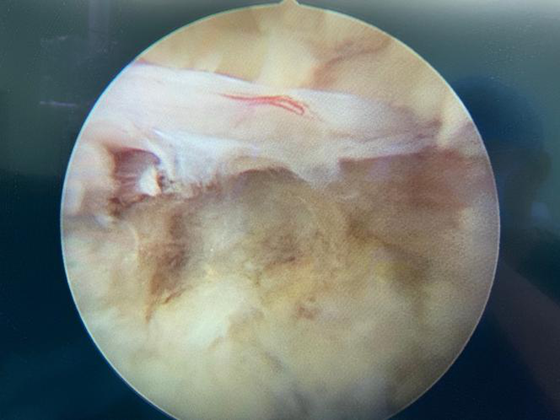

术中

患者入院后,在骨科主任张朝跃教授的指导下,经过周密的术前讨论及准备,陈芳田副主任医师团队在局麻下为患者实施了椎间孔镜下腰椎管减压手术(270°减压),术后患者双下肢胀痛即刻消失、麻木明显缓解。

随着腰椎椎间孔镜微创技术的应用,可在局麻下通过1厘米手术切口实现针对腰椎管狭窄症椎板减压及间盘摘除。极大地减小了手术创伤,术后当日患者即可下地行走,得到了患者的广泛认可。